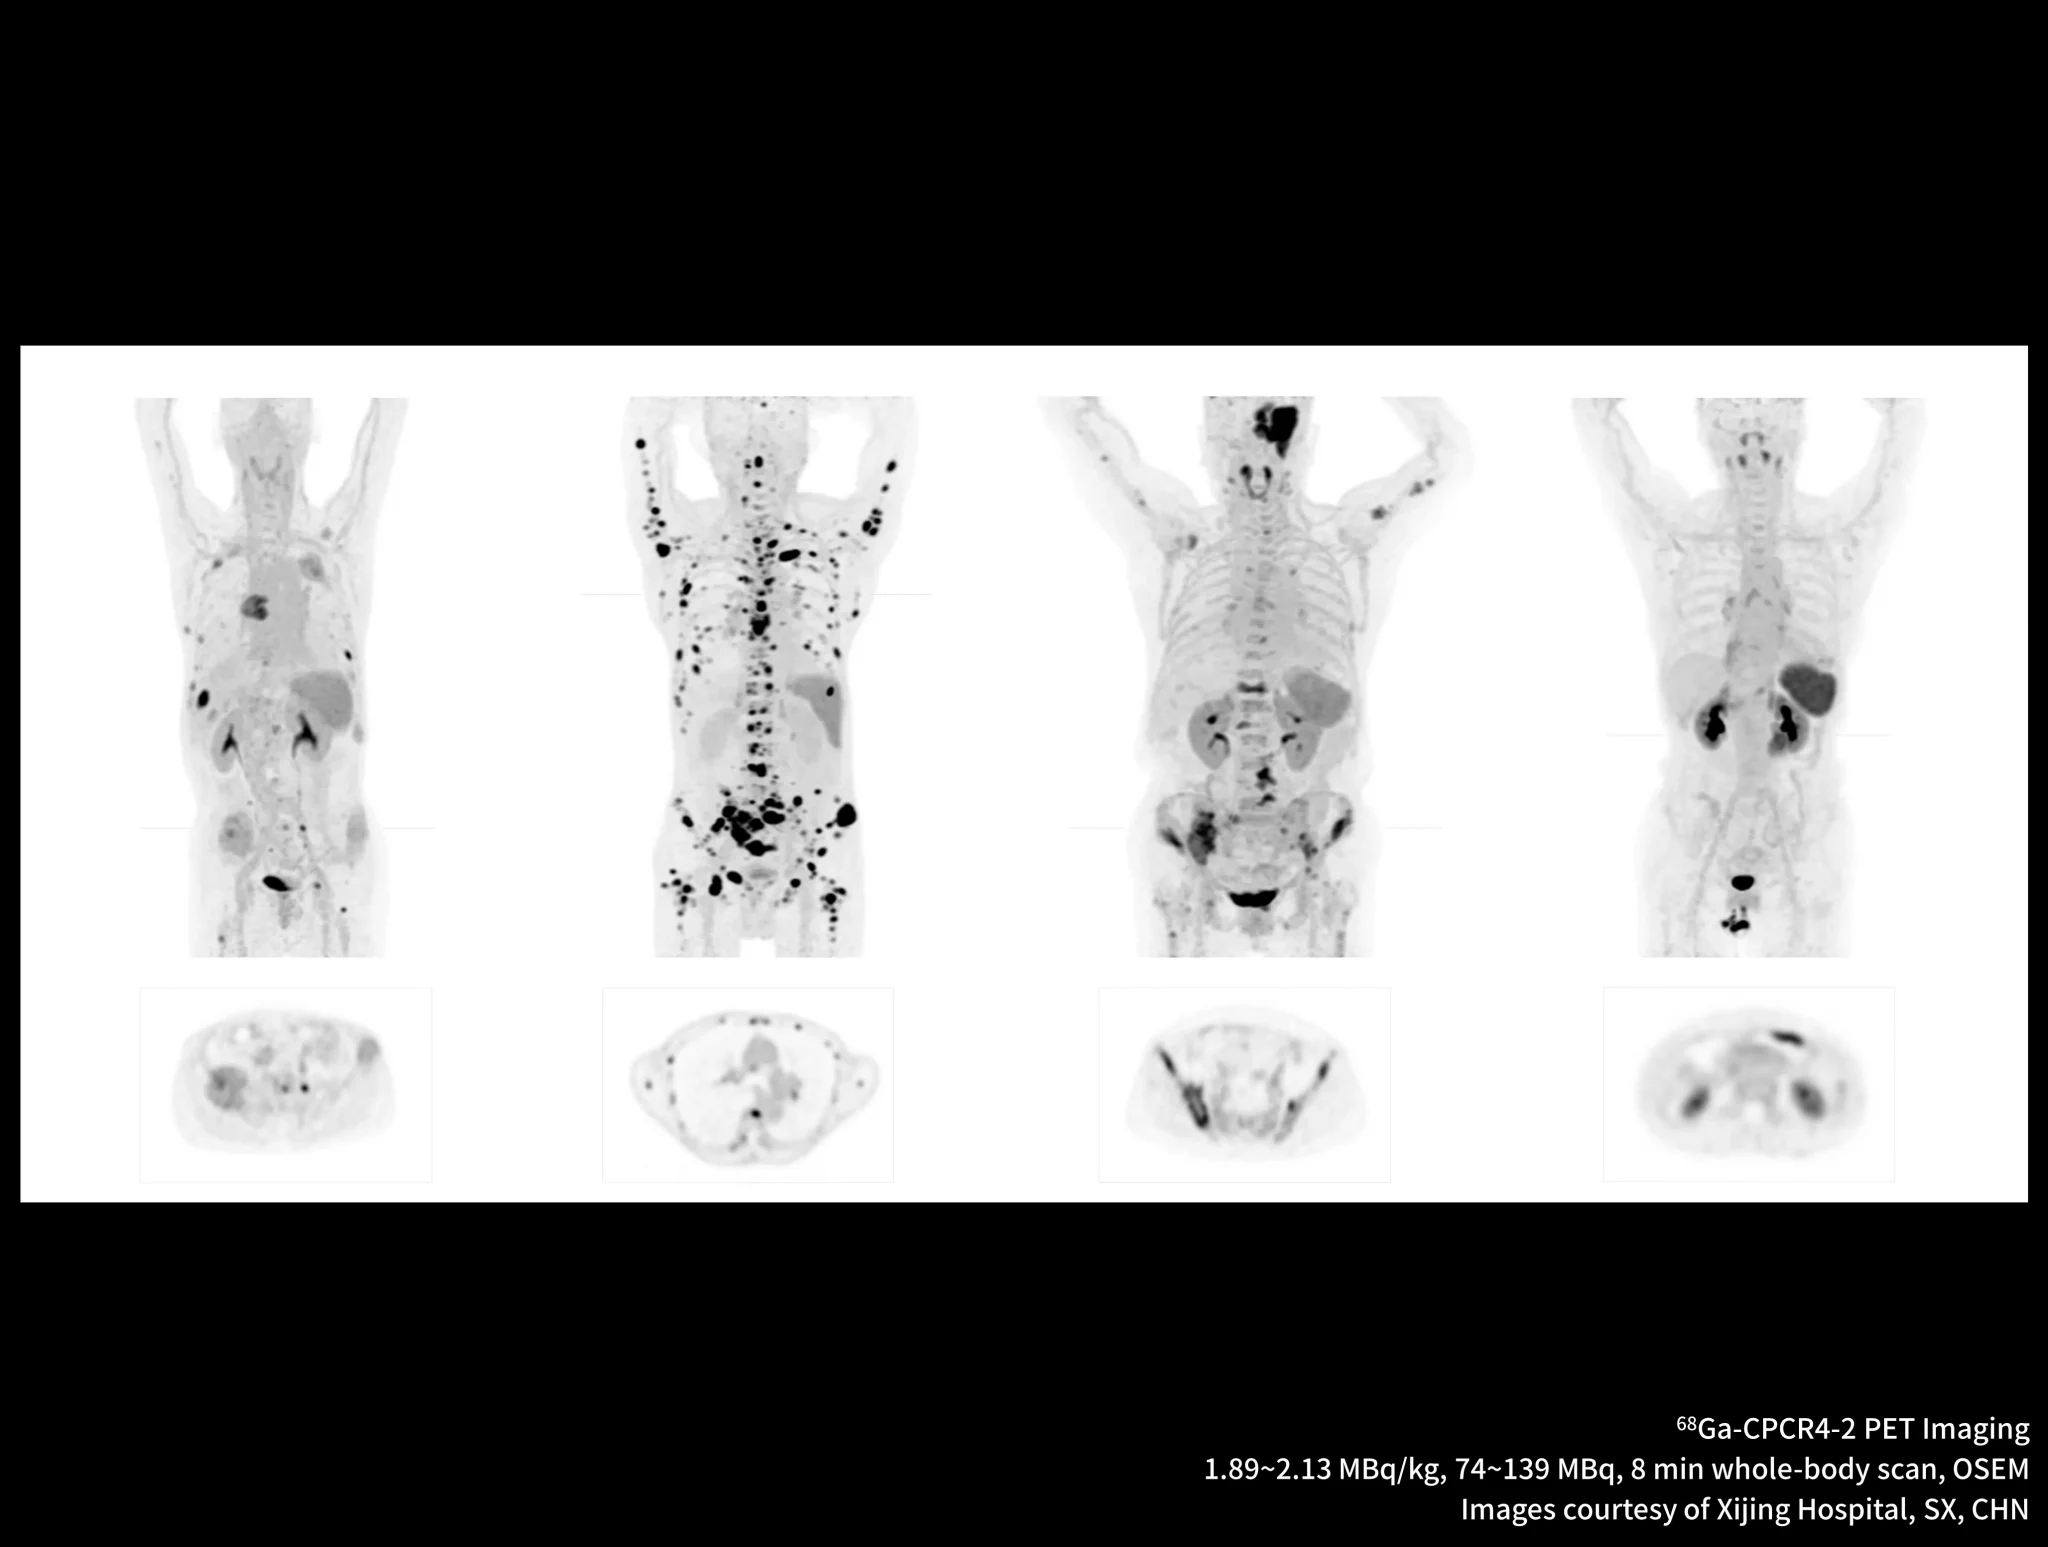

New-Tracer Imaging

Click on different tracers to see the images.